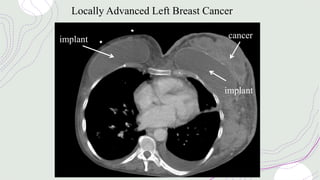

Locally Advanced Left Breast Cancer

implant cancer

implant

Locally Advanced LeftBreast Cancer implant cancer implant